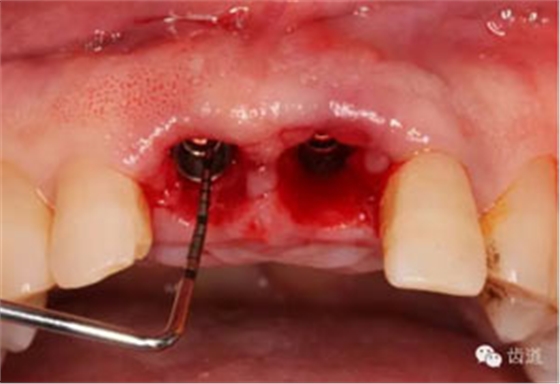

探查唇側(cè)骨板(約齦下3-4mm)

備洞軸向檢查

備洞完成